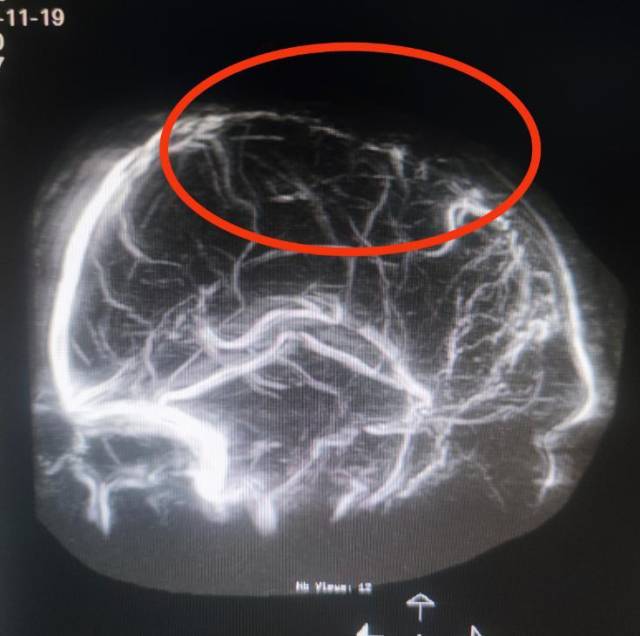

该院副院长鲁明接诊后,紧急安排脑血管相关检查,排查病因。MR检查结果提示患者右侧颞顶叶脑出血,周围存在继发缺血改变可能,进一步MRV(磁共振成像)结果显示上矢状窦中1/3次全闭塞,“元凶”正是颅内静脉窦血栓形成。

MRV(磁共振成像)结果显示上矢状窦中1/3次全闭塞。 受访者供图

阿豪随即接受手术治疗——DSA引导下上矢状窦中1/3次全闭塞球囊扩张成形+取栓术。术中复查造影见上矢状窦显影明显改善,经过脱水、抗凝治疗后,阿豪左侧肢体力量逐渐恢复。复查CT显示颅内出血较前吸收,后续还需要继续康复治疗。